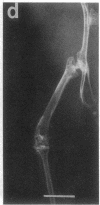

Studies were carried out on a line of transgenic mice that expressed an internally deleted COL2A1 gene and developed a phenotype resembling human chondrodysplasias (Vandenberg et al. 1991. Proc. Natl. Acad. Sci. USA. 88:7640-7644. Marked differences in phenotype were observed with propagation of the mutated gene in an inbred strain of mice in that approximately 15% of the transgenic mice had a cleft palate and a lethal phenotype, whereas the remaining mice were difficult to distinguish from normal littermates. 1-d- and 3-mo-old transgenic mice that were viable showed microscopic signs of chondrodysplasia with reduced amounts of collagen fibrils in the cartilage matrix, dilatation of the rough surfaced endoplasmic reticulum in the chondrocytes, and decrease of optical path difference in polarized light microscopy. The transgenic mice also showed signs of disturbed growth as evidenced by lower body weight, lower length and weight of the femur, decreased bone collagen, decreased bone mineral, and decreased resistance of bone to breakage. Comparisons of mice ranging in age from 1 d to 15 mo demonstrated that there was decreasing evidence of a chondrodysplasia as the mice grew older. Instead, the most striking feature in the 15-mo-old mice were degenerative changes of articular cartilage similar to osteoarthritis.